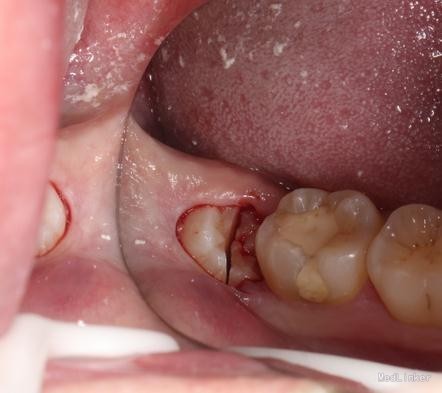

治疗计划:18、28,38拔除。 37重新充填。 48观察。 治疗:28局麻下拔除。 38阻滞下拔除。

拔牙常用牙挺的三步骤、 第一步、楔法:置挺时,插入牙根与牙槽骨之间,然后施力,边旋动,边楔入,使牙在牙槽窝内逐渐松动 ↓ 第二步、推法:将挺刃插在所拔牙牙齿的近中面或颊侧面与牙槽骨之间,使挺刃的凹面朝向根面凸面支靠在颊侧近中牙槽嵴上作为支点。用靠近冠部的挺刃推动所拔牙,使该牙受力后被推向远中或者舌侧而松动,但不包含使牙脱出牙槽的力。 其实说白了推法楔法差不多,只是用力方向幅度大小不同。 楔是向下楔入,推是增大间隙。 第三步、挺法:置放方法与推法一致,只是用力方向变了。向远中面方向旋动牙挺时,使紧贴颈部根面的挺刃向所患牙使力,使其受力后被挺向远中并向合面方向移动。再逐渐加大牙挺旋动的幅度,并将挺刃逐渐向牙槽内插入(配合楔法),牙的松动度也随之增大。最后,使该牙将向合面与远中的合力方向松动脱位。